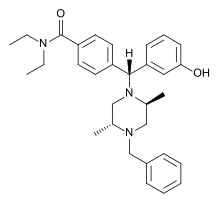

Diphenylmethylpiperazines